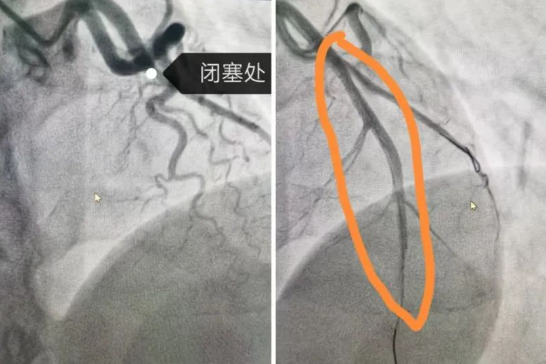

8點(diǎn)30分,導(dǎo)管室迎來(lái)了第一批患者,兩個(gè)手術(shù)間同時(shí)啟動(dòng)。第1手術(shù)間接診的是一位31歲的急性心肌梗死男性患者,他因胸痛和呼吸困難被緊急送醫(yī)。冠狀動(dòng)脈造影顯示,患者的左冠前降支完全閉塞,情況十分危急。在院長(zhǎng)隋立有的帶領(lǐng)下,醫(yī)護(hù)團(tuán)隊(duì)緊密配合,迅速為患者實(shí)施了PCI手術(shù)。經(jīng)過(guò)緊張而有序的操作,成功開(kāi)通了閉塞的血管,并植入一枚支架,恢復(fù)了血流,改善了心肌供血,挽救了這位年輕患者的生命。